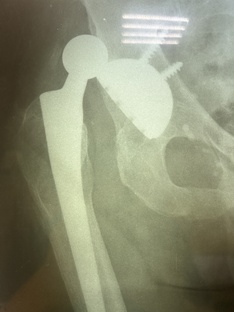

КАК ЖИТЬ ПОСЛЕ ОПЕРАЦИИ ПО ПРОТЕЗИРОВАНИЮ ТАЗОБЕДРЕННОГО СУСТАВА

Общие вопросы Ежегодно в России проводят свыше 250 000 операций по замене тазобедренного сустава, преимущественно у пациентов старше 60 лет. Однако патология часто начинают развиваться уже в молодом возрасте особенно от травм и последствий асептического некроза головки тазобедренного сустава. Когда необходима операция по протезированию тазобедренного сустава? Медицинские показания: - постоянная боль и дискомфорт в области тазобедренного сустава - ограничение движений, невозможность выполнять физические...